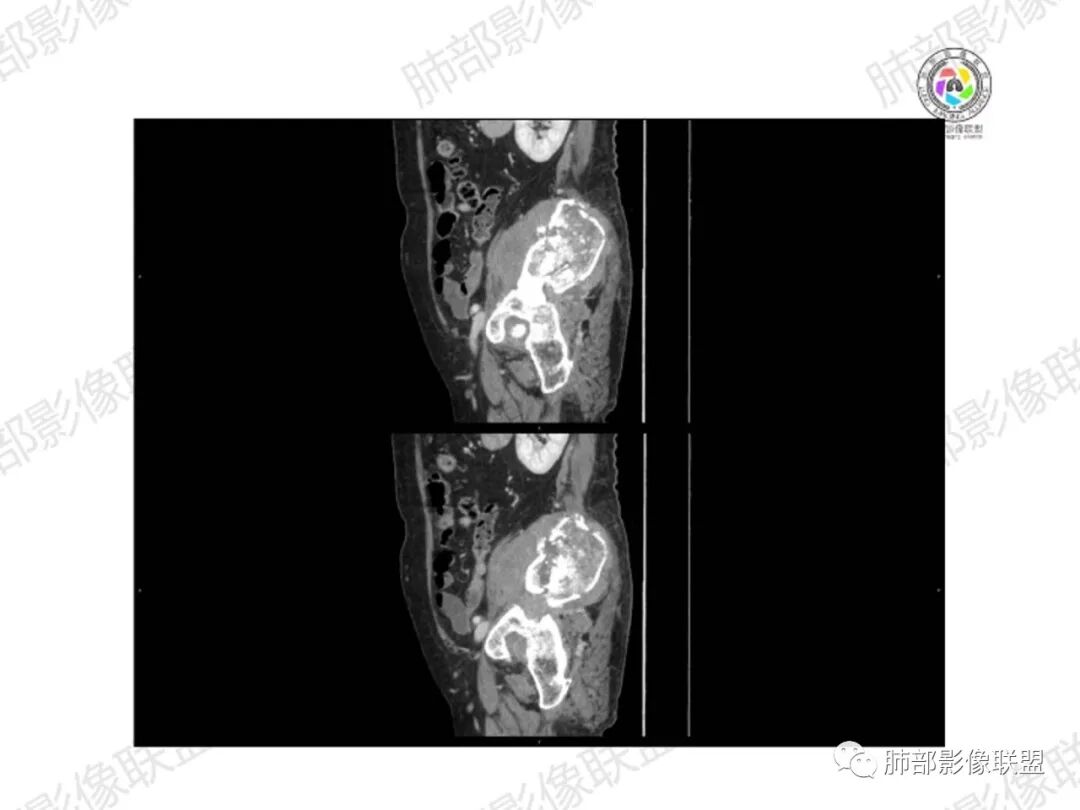

2.右髂骨轻度变形伴广泛骨质吸收破坏,边界不清且突破骨皮质。近中线区以溶骨性破坏为主,髂骨翼一侧则成骨性改变明显,骨表面见垂直骨针或花边样高密度瘤骨。

3.患骨多处皮质断裂,符合病理性骨折。注意折端可能会形成骨痂,但本例无论是形态还是部位都不符合骨痂。

4.患骨两旁(即盆骨内外)见边界不清的较大范围软组织快影,其间偶见骨化影。

1.边界不清的骨质吸收破坏,溶骨明显,骨皮质突破,软组织肿块,种种迹象表明其恶性无疑!

2.但注意这是有“成骨”的恶性骨肿瘤!我们知道老年患者的骨原发性恶性肿瘤“成骨”非常少见。少数转移瘤可为成骨型或混合型,女性患者如乳腺癌骨转移等。在男性,最典型的成骨转移是前列腺癌。

本例右侧髂骨具有较为典型的“骨肉瘤”影像学特征,有边界不清的吸收破坏、有新生骨、形成软组织肿块等等。